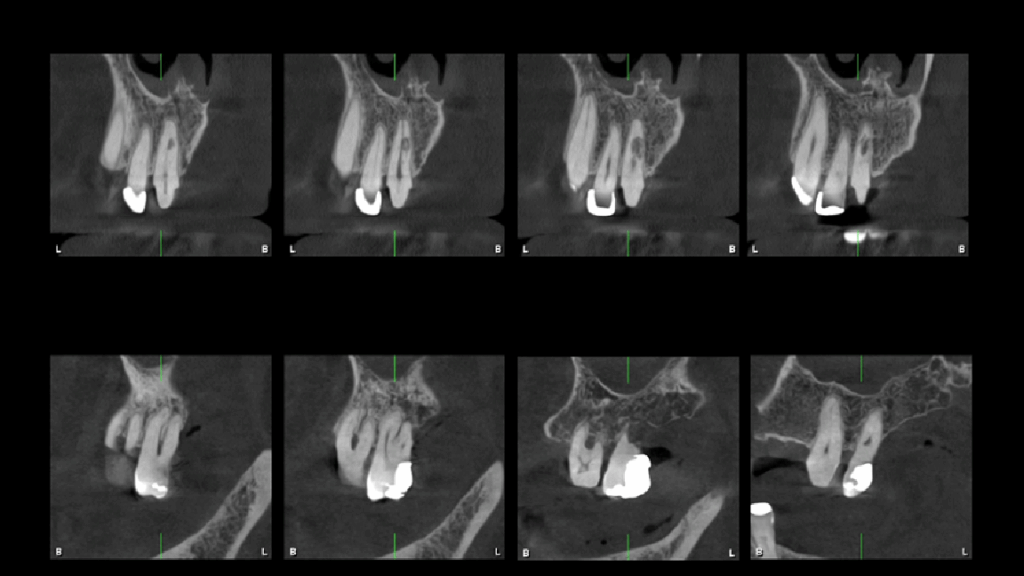

A la evaluación de la tomografía cone beam de campo mediano (FOV = 10 x 10) se observa en la pieza 11 la presencia de una imagen hipodensa de forma irregular localizada a niel de tercio medio radicular y que se compromete la dentina radicular por mesial y palatino, asimismo se observa la pieza 27 que además de la restauración presenta una imagen hipodensa en raíz palatina a nivel de tercio medio radicular y finalmente un trazo de fractura vertical por distal que compromete la zona de furcación y ocasiona un proceso osteolítico interradicular.

CORTES TANGENCIALES